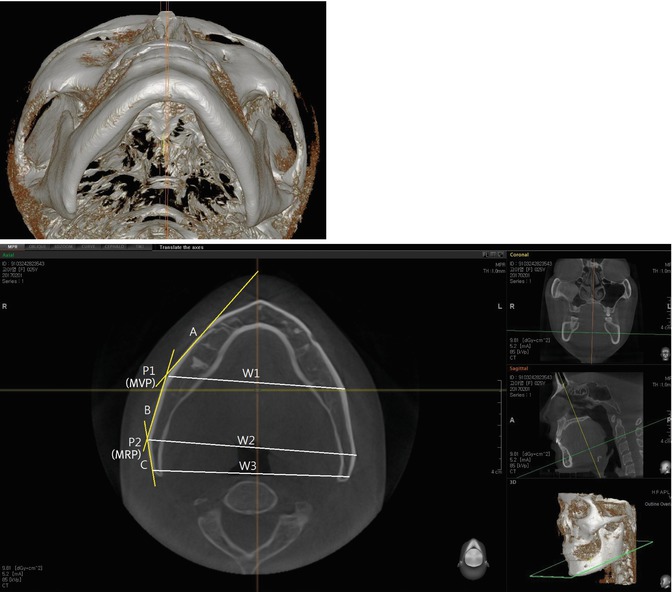

Fig. 7.5

The mandible of incurved type. (Upper) Three-dimensional submento-vertex view of the mandible. (Lower) Axial view. The posterior ramus tilts inward. The maximum ramus point is the most protruded area, and the bi-ramus (W2) distance is the widest area comparing bigonial distance (W3)

Regarding the mandibular body when viewed on computed tomography, the widest point is the intersection of the surface line of the mandibular body (A) and ramus (B) (Figs. 7.3, 7.4 and 7.5). This point (P1) is usually the thickest area, the average thickness of which is 17.8 mm, while that at the posterior angle area was 6.4 mm. This point is named as the maximum body point (MBP).

Three lines, two points, and three widths are used to describe the shape of the mandible on computed tomography (Figs. 7.4, 7.5 and 7.6). The line on the mandibular body surface is the body surface line (A), and the one on the ramus surface is the ramus surface line (B). In incurved type of the mandible, there is the third line in the posterior ramus, named as posterior ramus surface line (C). The maximal body point is marked by the widest and usually the thickest point on computed tomography and the intersection of the body surface line and ramus surface line (P1). The maximal ramus point is described as the intersection of the ramus surface line and posterior ramus surface line in the submento-vertex view (P2).